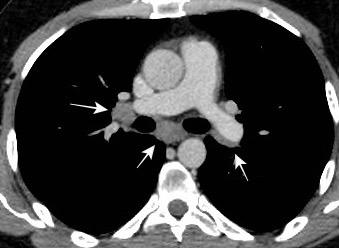

Triada de Garland

Ganglios paratraqueales derechos e hiliares bilaterales

95% de pacientes tienen ganglios hiliares bilaterales aislados o con afectación mediastínica (espec. paratraqueal derecho).

Criado E et al. Pulmonary sarcoidosis: typical and atypical manifestations at high-resolution CT with pathologic correlation. Radiographics. 2010